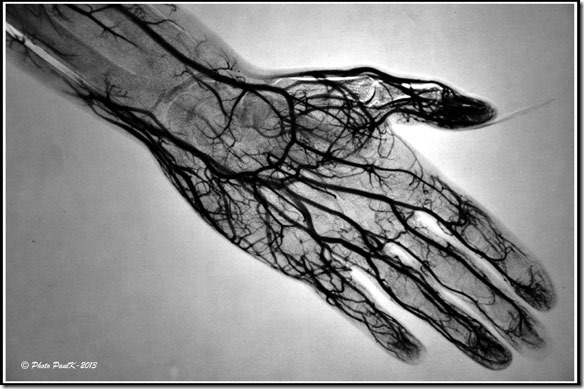

Main-Masque

En radiographie, la technique du masque est surtout utilisée lors d’examens particuliers destinés à explorer le système artériel ou veineux.

Pour radiographier le système artériel ou veineux, il est nécessaire d’injecter un produit qui soit opaque aux rayons X.

C’est ce que l’on appelle communément, le produit de contraste.

Masque-ArterioAL’inconvénient de ce procédé est que les parties du corps les plus denses, les os en particulier, sont aussi opaques aux rayons X.

Cela rend donc la lecture et l’interprétation des radios plus délicates.

L’astuce photographique consiste dont à masquer sur le cliché, ces éléments indésirables.

En prenant une radiographie de la zone à examiner avant toute injection, nous obtenons une image dont il est facile d’obtenir une image positive avec un film particulier (masque).   —> Ce qui est blanc devient noir et réciproquement.

Il sera alors facile de superposer ce masque au cliché obtenu, après injection du produit de contraste, pour obtenir une nouvelle image par soustraction, sur laquelle n’apparaîtront que les éléments attendus.